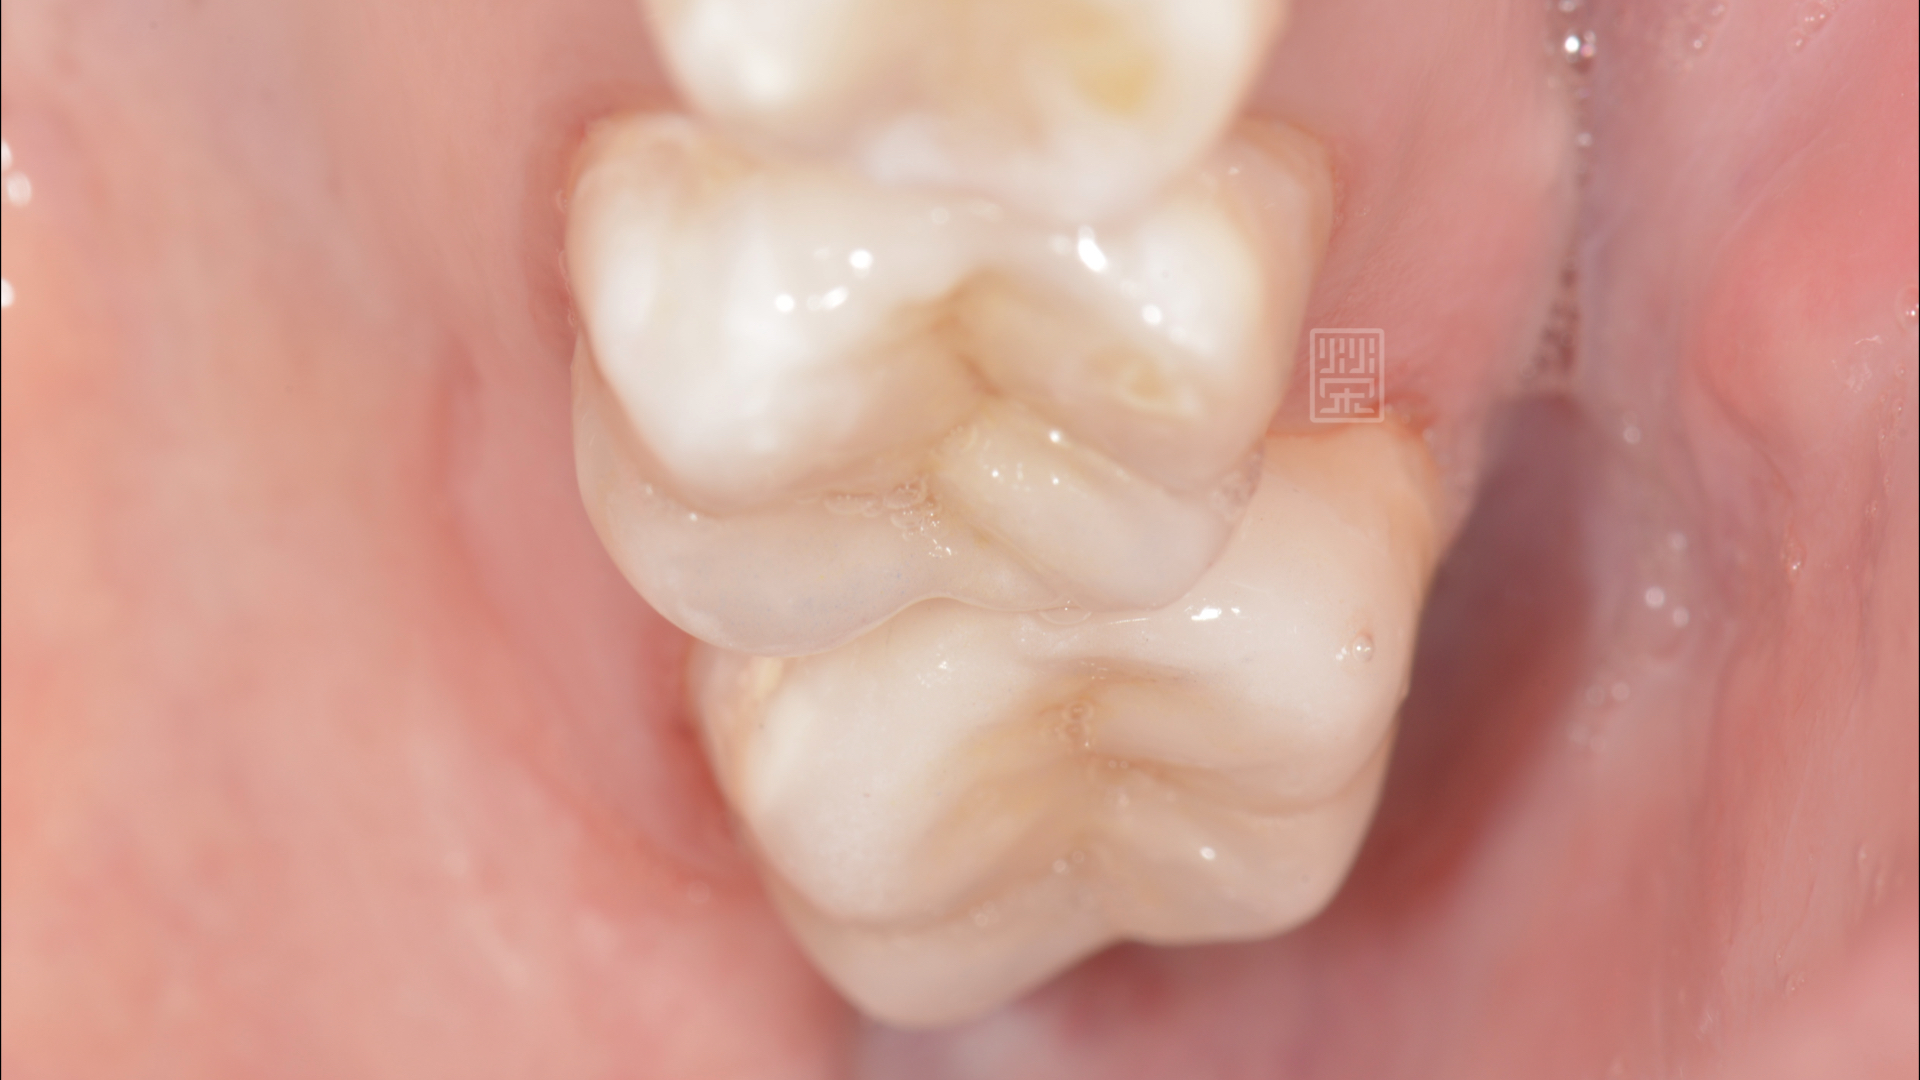

全瓷嵌體完成

在清除蛀牙、舊的填補誤之後,利用全瓷黏著贋復物,恢復型態與功能,讓陳小姐能夠自在的享用美食。